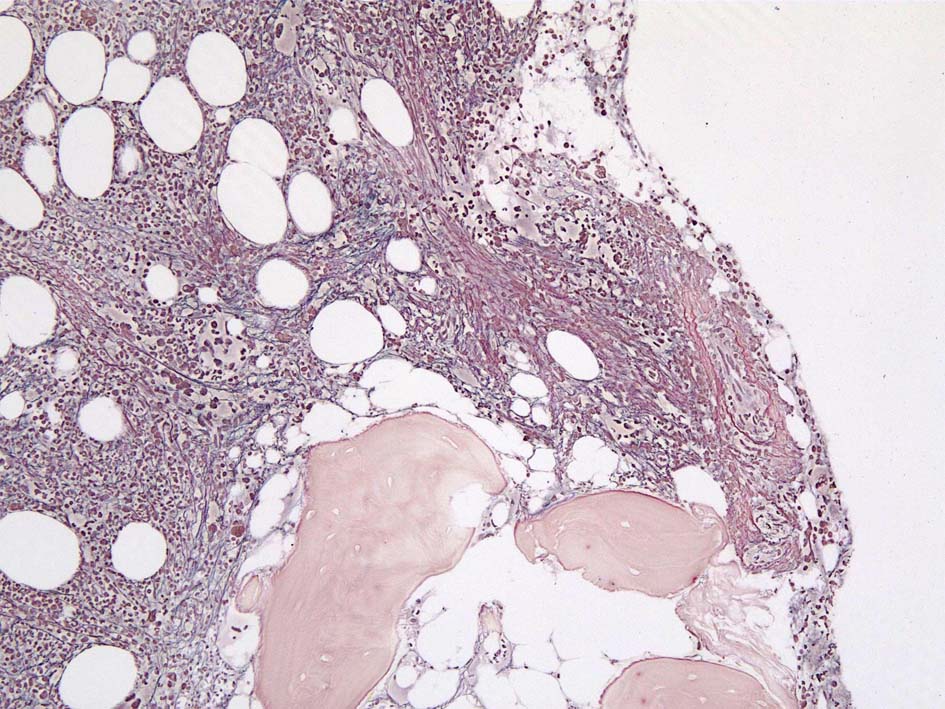

Case02; Meylofibrosis, overt fibrosis

77year-old female. 40歳時polycythemia veraと診断されていた.

[注] この症例は詳細は不明であるが, 過去にPVと診断されているため, PVに伴う二次性のmyelofibrosisの診断になる.

黒染する弾性線維の増生のほか, 赤く染まる膠原線維の増生が確認される. MF-2 fibrosis. 鍍銀染色の核染色をすると膠原線維の赤染がわからなくなるので行わない.